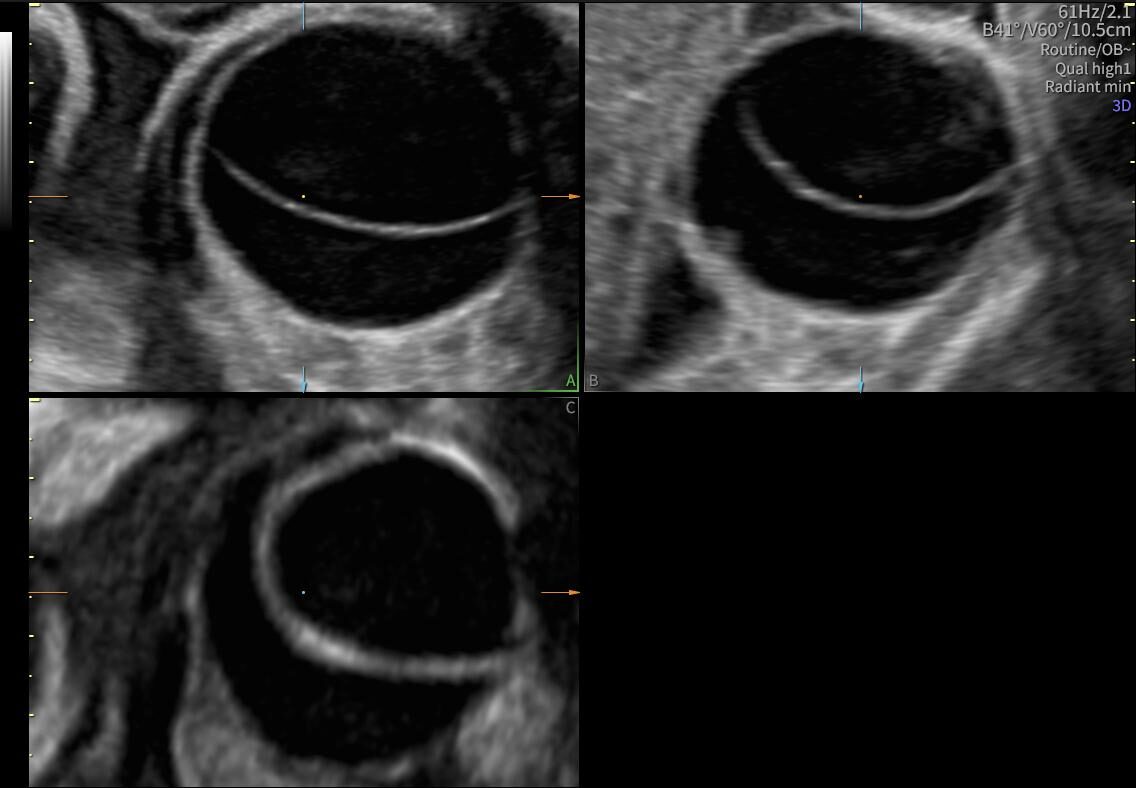

La ecografía ginecológica es un estudio por imágenes no invasivo que permite evaluar de forma precisa el útero, los ovarios y el sistema reproductor femenino. Es una herramienta fundamental para la detección temprana de alteraciones ginecológicas, el seguimiento de tratamientos y los controles preventivos.

En OBGYN Perú, realizamos ecografías ginecológicas con equipos de alta resolución, garantizando resultados confiables y una atención médica especializada.